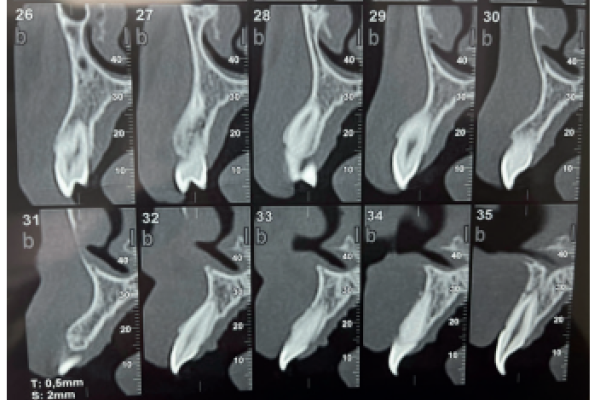

Retención de segundos molares mandibulares: evaluación mediante CBCT y consideraciones terapéuticas ante un caso clínico

Diagnóstico radiográfico de los caninos maxilares incluidos. Comparación entre dos y tres dimensiones

Radiographic diagnosis of impacted maxillary canines: Comparison between two and three dimensions

Anatomía de la arteria alveolar posterior superior (AAPS): estudio de 32 CBCT